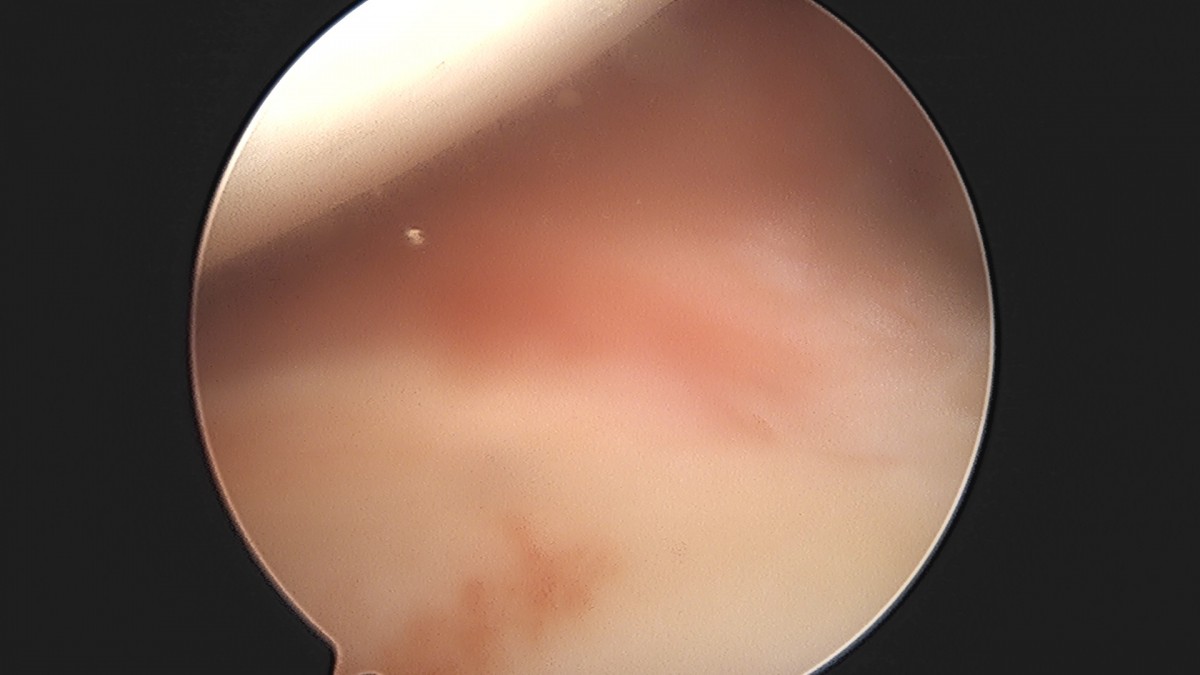

이재상원장님 어깨 견봉하 감압술 및 석회 제거술 이형O 환자

작성자 최고관리자 댓글 0건 조회 746회 작성일 25-09-16 15:40